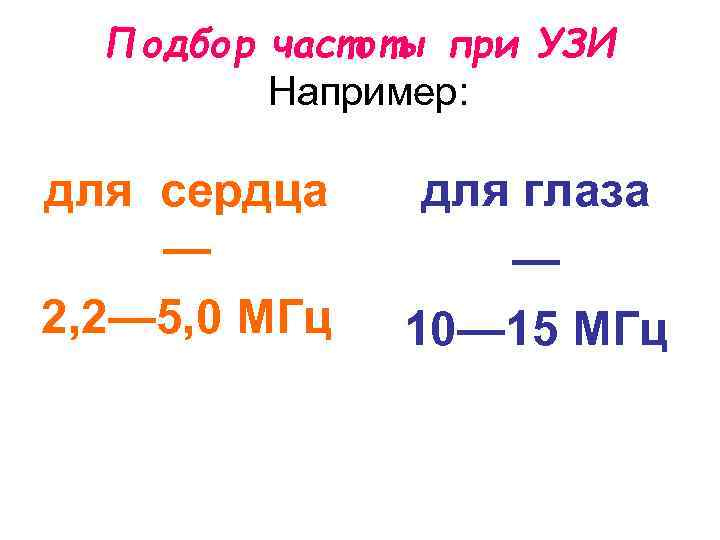

Подбор частоты при УЗИ Например: для сердца — 2, 2— 5, 0 МГц для глаза — 10— 15 МГц

Подбор частоты при УЗИ Например: для сердца — 2, 2— 5, 0 МГц для глаза — 10— 15 МГц